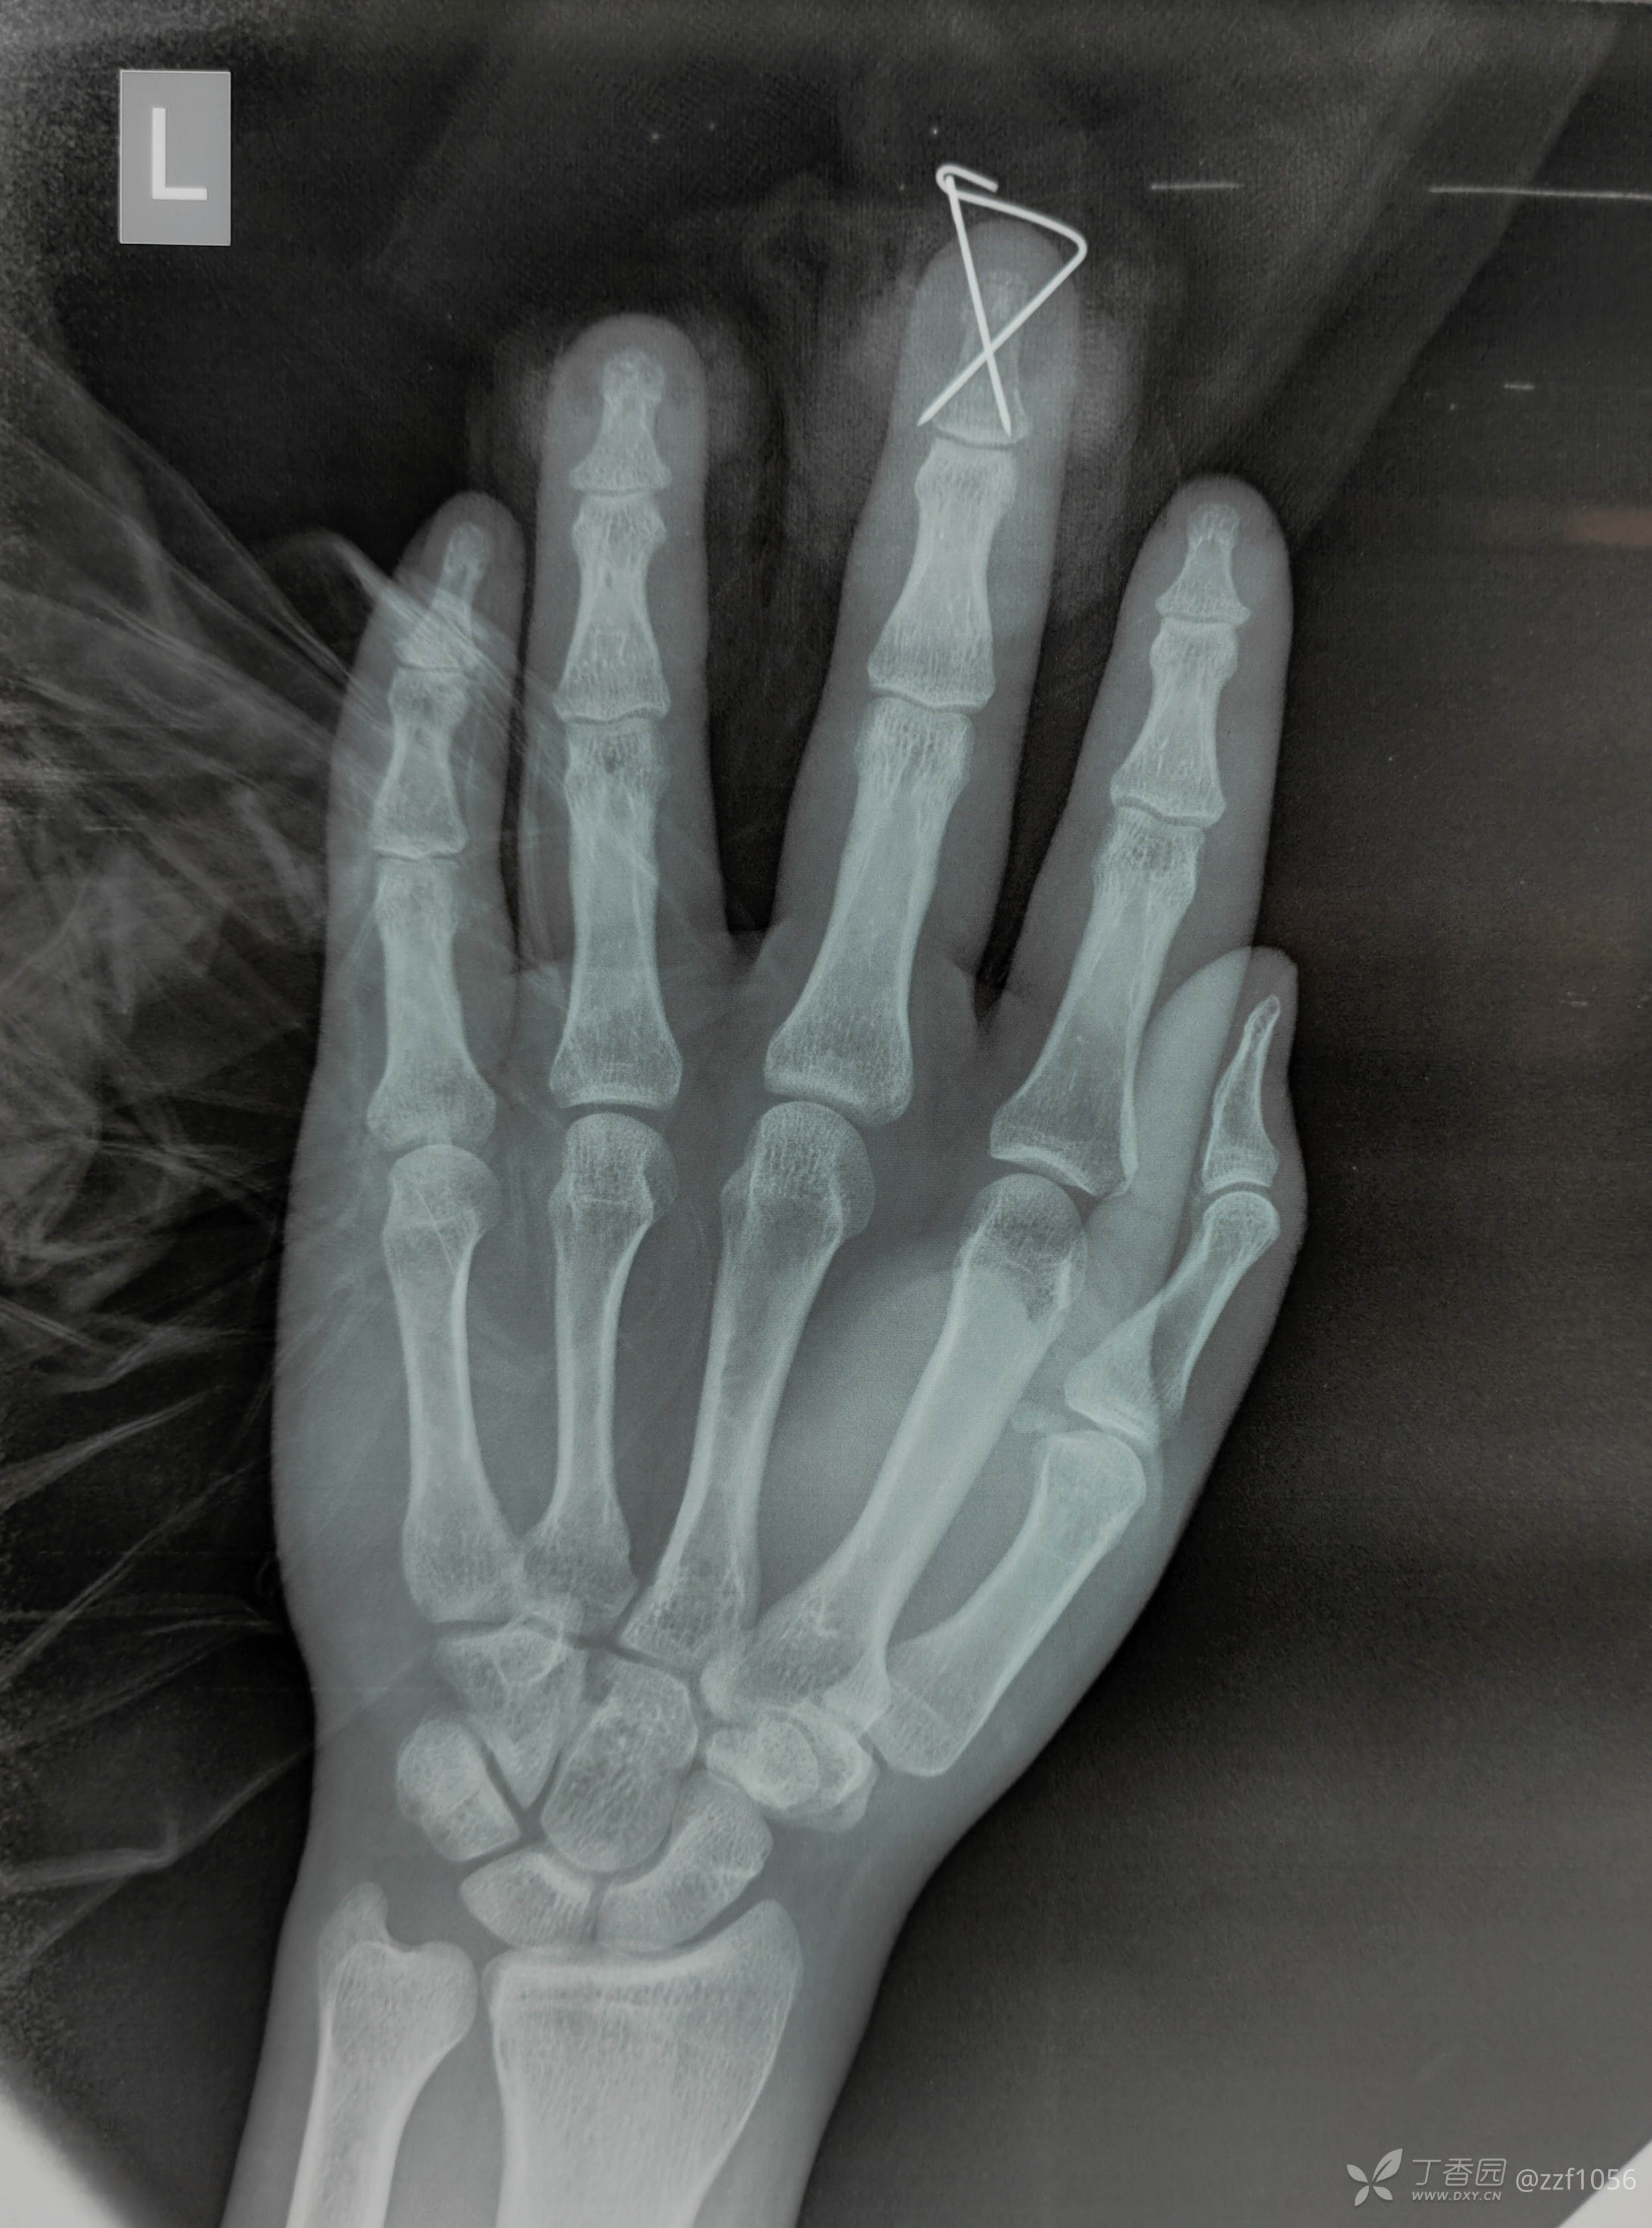

甲床根部破裂嵌入折端,清理后撬拨复位,怎么固定?克氏针一枚还是两枚?纵行还是交叉?需要外固定吗?

指甲是否需要回植?回植的优势?回植的技巧?回植后就安全吗?回植的必要性?